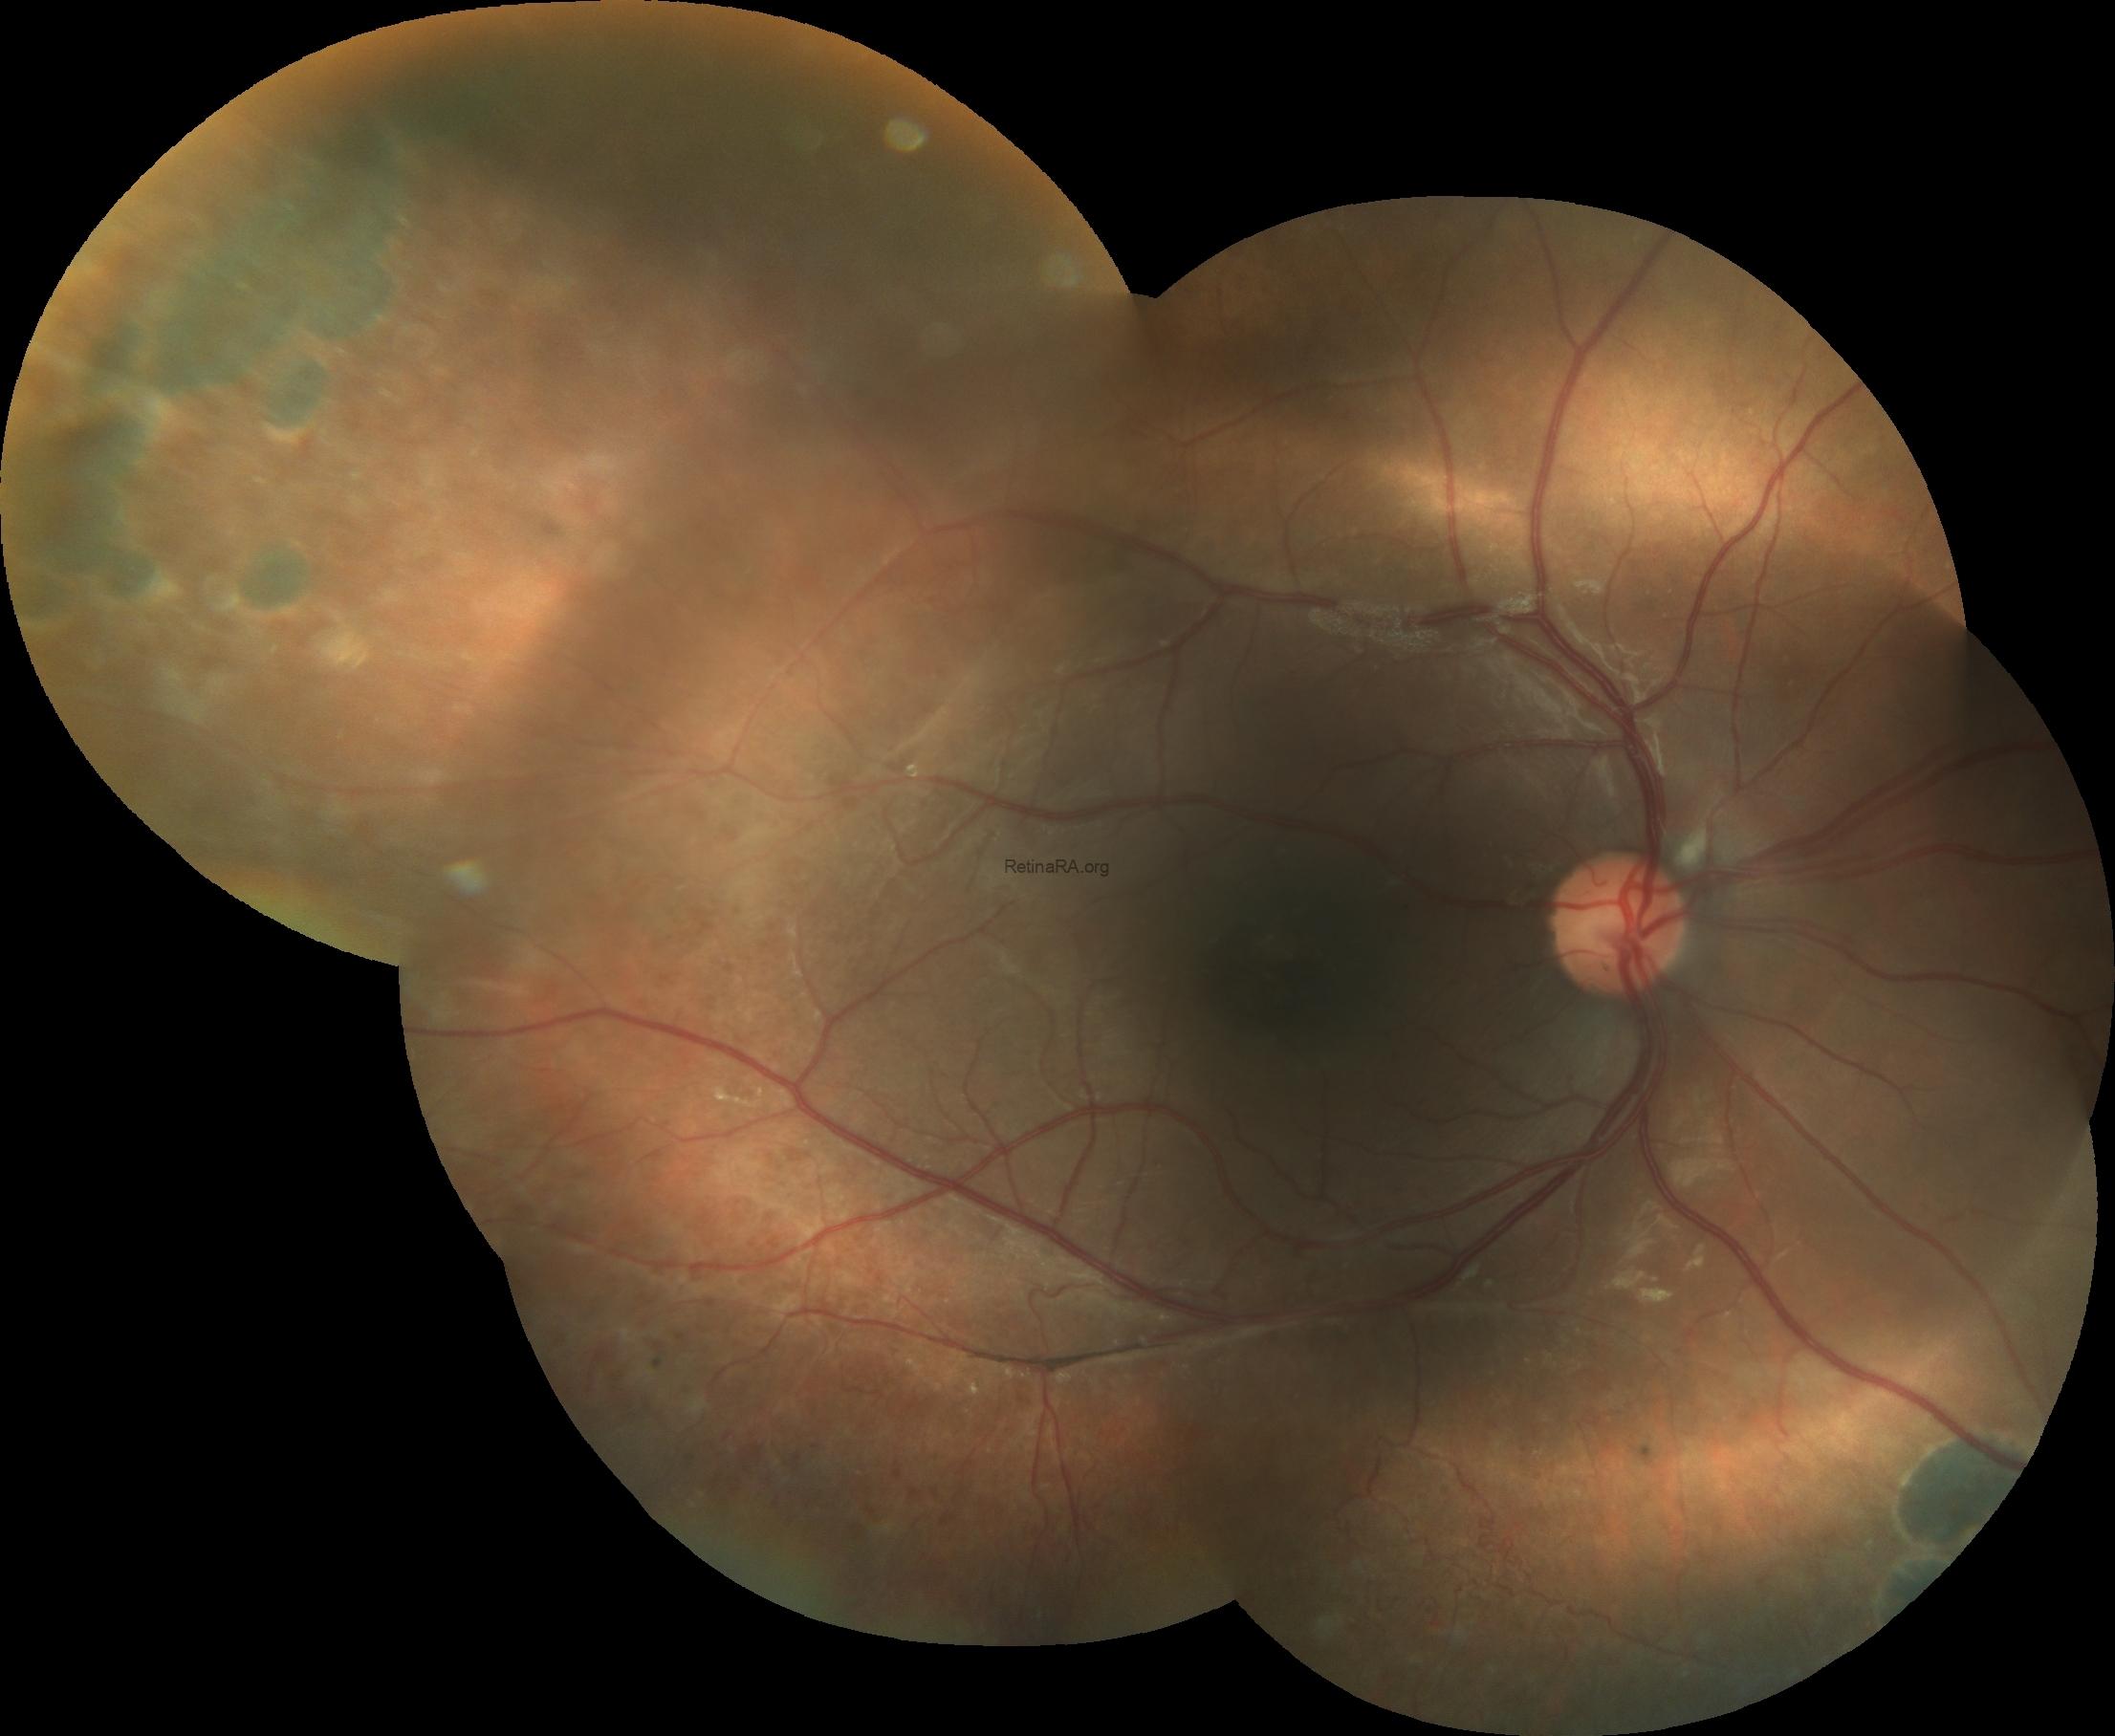

Fundus imaging revealed an abnormal foveal reflex with cystic lesions in both maculae. The right eye showed peripheral old laser scars and dome-shaped schisis, while the left eye demonstrated foveal schisis with a characteristic spoke-wheel pattern radiating from the fovea, along with an inferotemporal peripheral schisis.

Based on these multimodal imaging findings, a preliminary diagnosis of X-linked retinoschisis was made, which was later confirmed by genetic testing revealing an RS1 gene mutation.